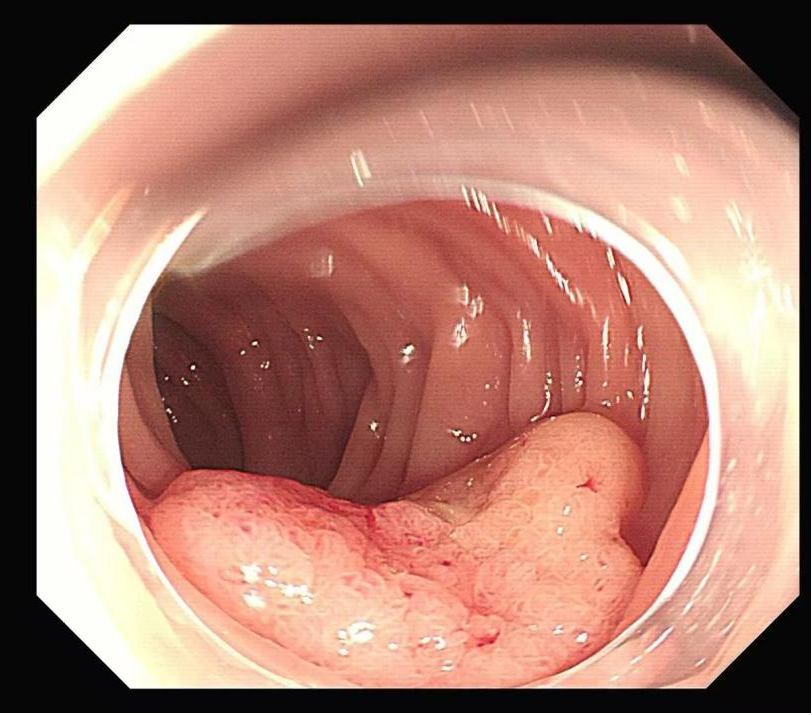

手术过程中,申星杰教授与医院内镜团队密切配合,操作精准高效,仅用 30 分钟便一次性完整切除张女士直肠黏膜病变部位。术后,张女士病情稳定,未出现任何手术相关并发症,目前恢复状况良好。

图解手术过程